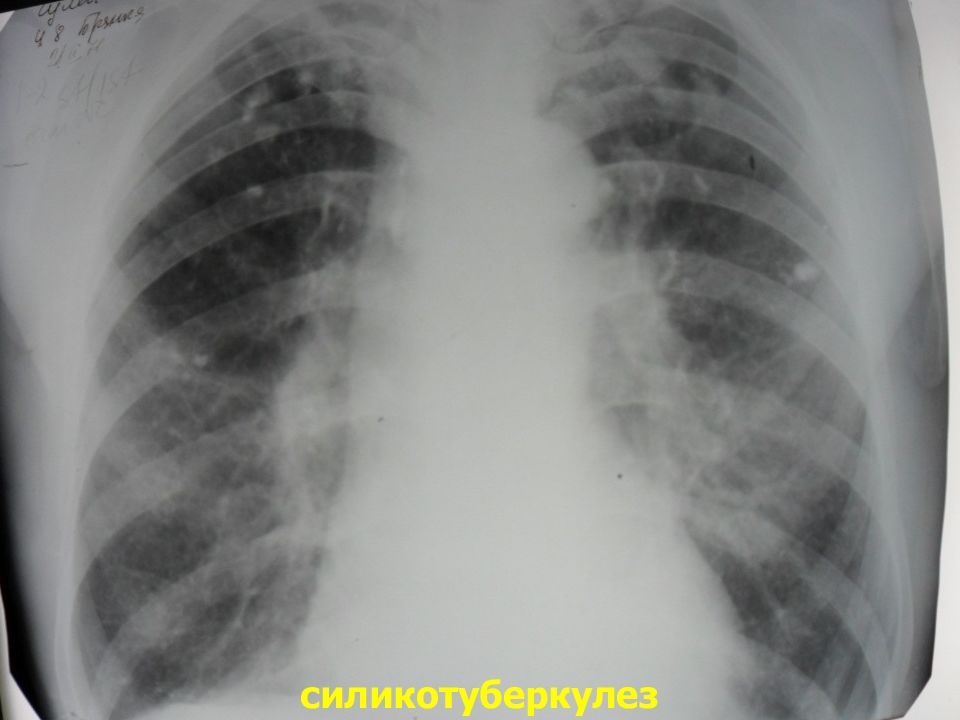

Рентгенологические изображения и синдромы патологии легких

Раздел: Кадры-подсказки